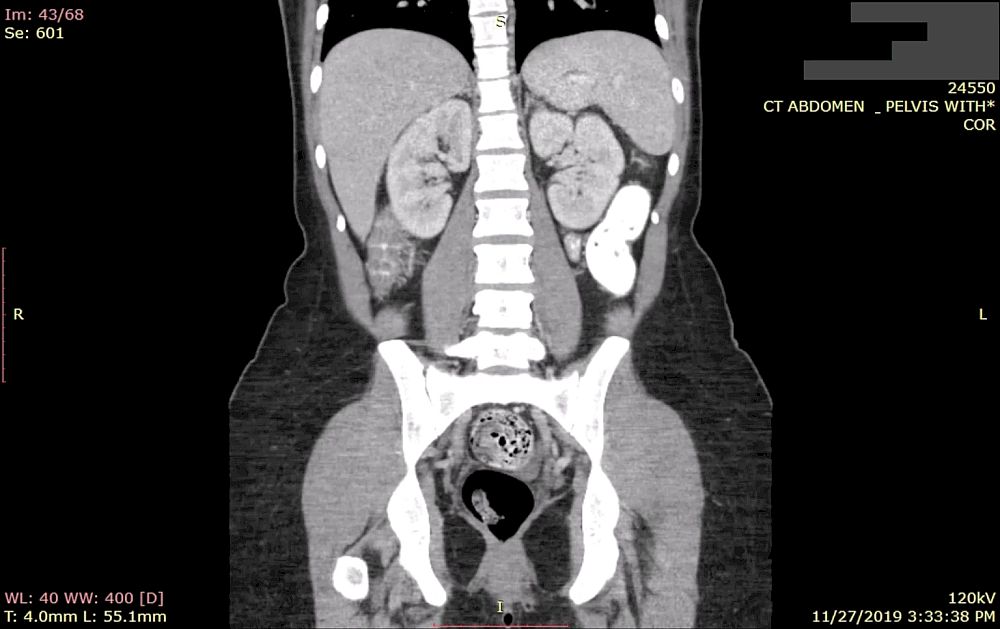

每天,数以百万计、包含患者个人健康信息的医学图像都会涌入到互联网上。数以百计的医院、医疗工作室和影像中心都在运行着不安全的存储系统,以至于任何拥有互联网连接的用户都可以通过免费下载的软件来访问全球超过10亿例患者的医学图像。

在所有曝光的图像(包括X射线,超声波和CT扫描)中,约有一半属于美国患者。尽管安全研究人员就该问题向医院和医生办公室发出多次警告,但依然有很多人忽略了他们的警告,并继续暴露患者的私人健康信息。德国安全公司Greenbone Networks的研究工作的Dirk Schrader表示:“这种情况每天都在恶化。”该公司过去1年都在监控泄漏服务器的数量。

去年9月份,Greenbone已经发现了有超过2400万例患者的7.2亿张医学图像在网络上被曝光。然而两个月之后,暴露的服务器数量增加了一半以上,达到3500万例患者检查,暴露了11.9亿次扫描,这严重侵犯了患者的隐私。